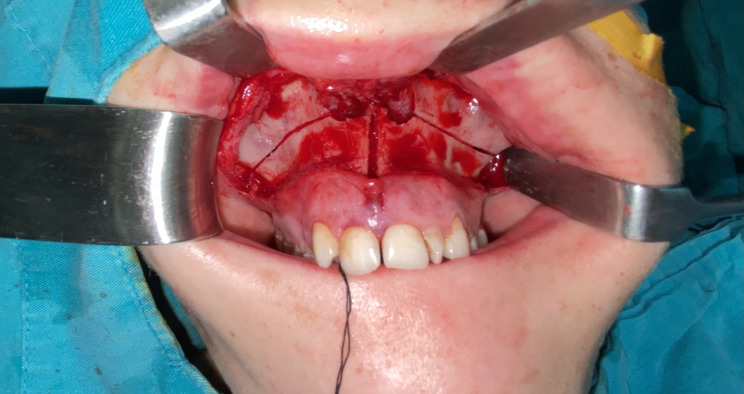

Background: This study aimed to evaluate the effects of surgically assisted rapid maxillary expansion (SARME) and rapid maxillary expansion (RME) groups on midpalatal suture (MPS).

Methods: CBCT records who underwent RME and SARME between 2013 and 2024 were included in the study. CBCT axial sections taken preoperatively (T0) and after a 3-month retention period (T1) were evaluated using the MPS. Fractal Analysis (FA) method using the ImageJ program and compared between the groups.

Abstract Image